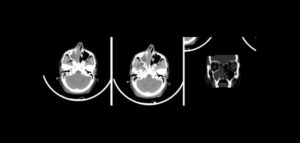

Paciente masculino con 19 años de edad, es referido al Instituto de Diagnóstico Maxilofacial (IDM) para evaluación tomográfica por presencia de lesión en maxilar superior